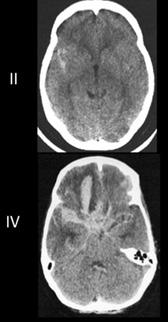

Diagnóstico

Al igual que el ECV isquémico, la prueba inicial siempre debe ser la neuroimagen sin contraste. La tomografía sin contraste es el gold estándar diagnóstico y es mucho más sensible y específica que la resonancia para detectar sangrado.

Tabla 2. Clasificación de Hunt y Hess Tabla 3. Escala de Fisher Figura 6. TAC: Hemorragia subaracnoidea (HSA) (Escala de Fisher)